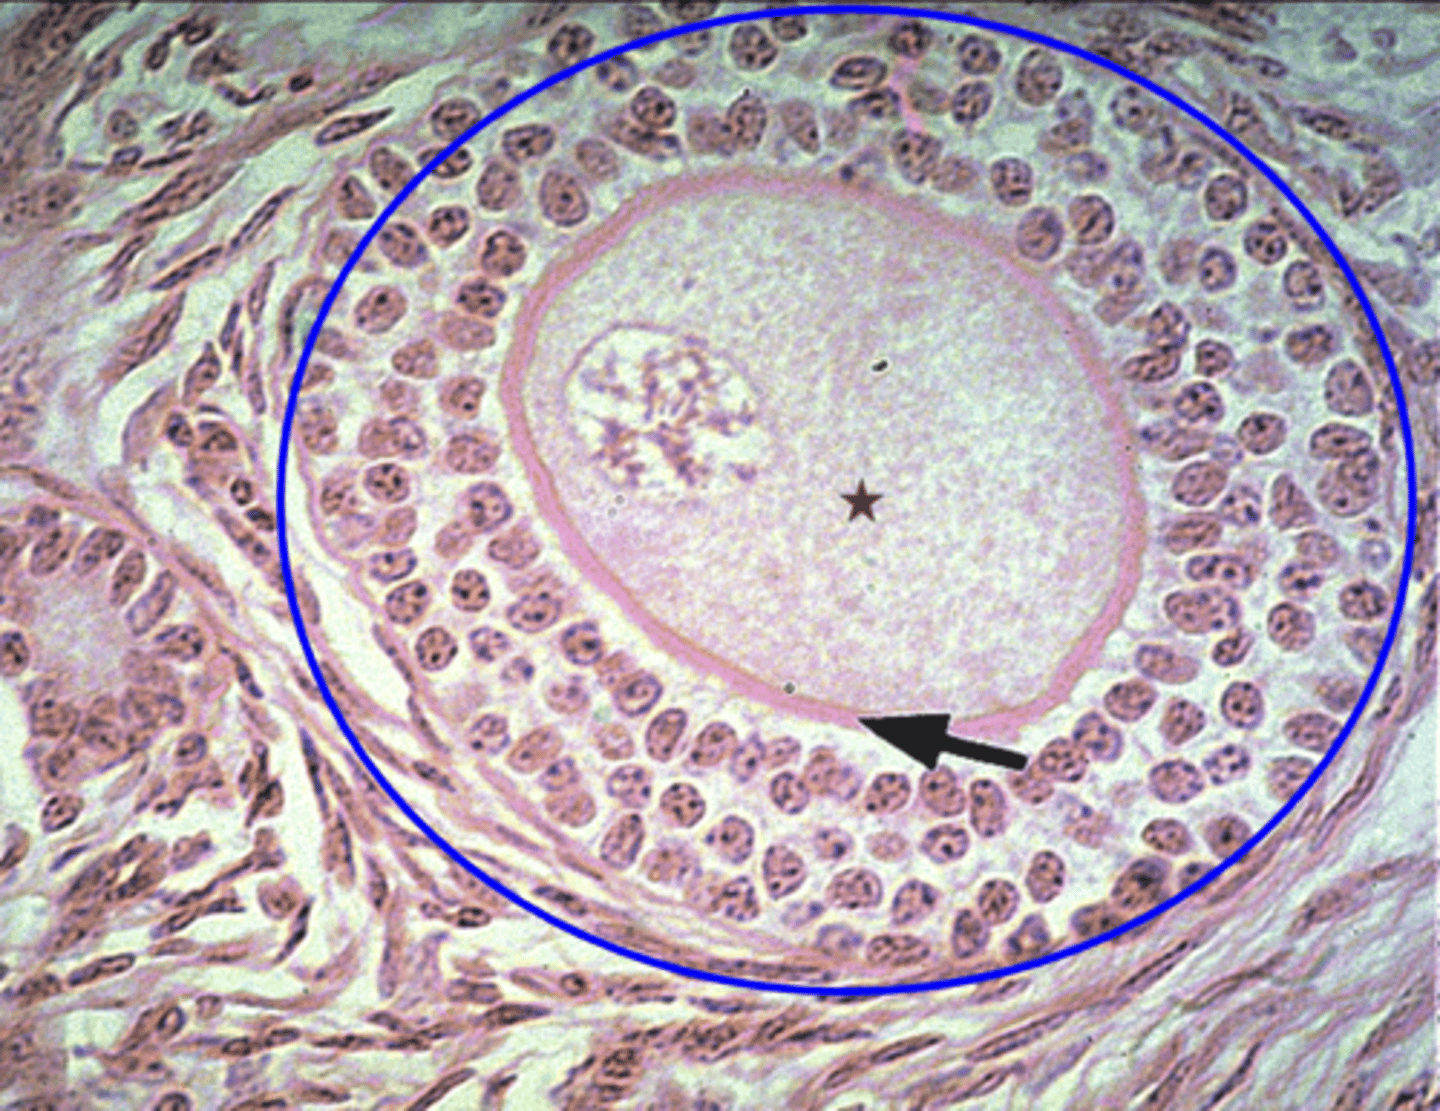

What is the green circle?

Multilaminar primary follicle

What is the blue outline?

Primary oocyte

What is the red star?

What is the blue circle?

secondary follicle

Has a small antrum?

Graafian follicle

Has a large antrum

Cells make estrogen

Function of the secondary follcile?

The follicle undergoes ovulation

Function of the graafian follicle?

What secretes the most estrogen?

What contains the oogonium?

Primordial follicle

Whats found in the fetus?